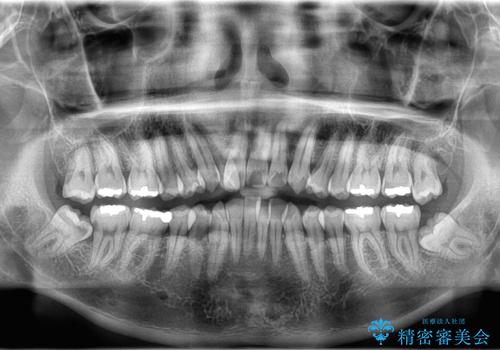

- 「歯のデコボコと前歯が引っ込んでいるのを治したい」を主訴に来院された患者様です。

デコボコの量が多かったため上下左右4を抜歯してワイヤー矯正で治療を行いました。

正面から見たときに右上2が全く見えないくらい、右上2が後ろに引っ込んでいる状態でしたが綺麗に並べる事が出来ました。